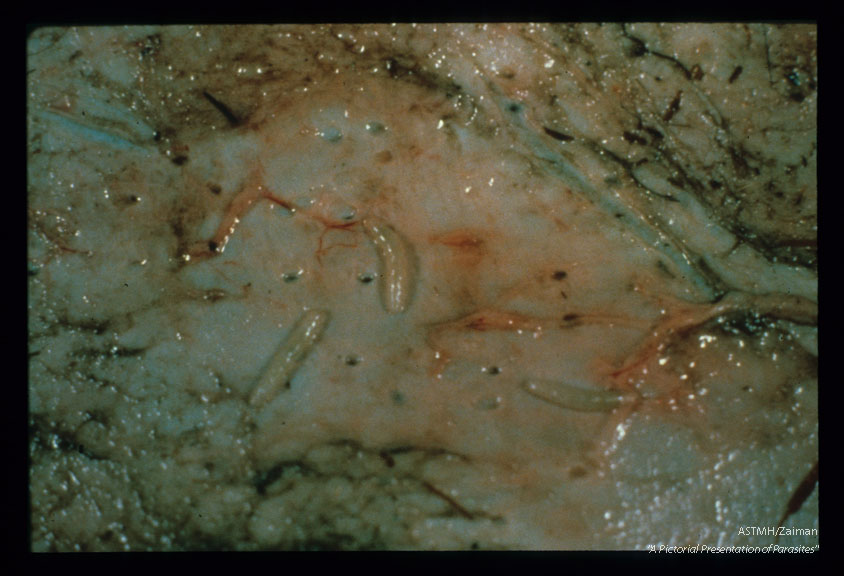

Cutaneous myiasis in bison skin.

Hypoderma tarandi

Description: Cutaneous myiasis in bison skin.